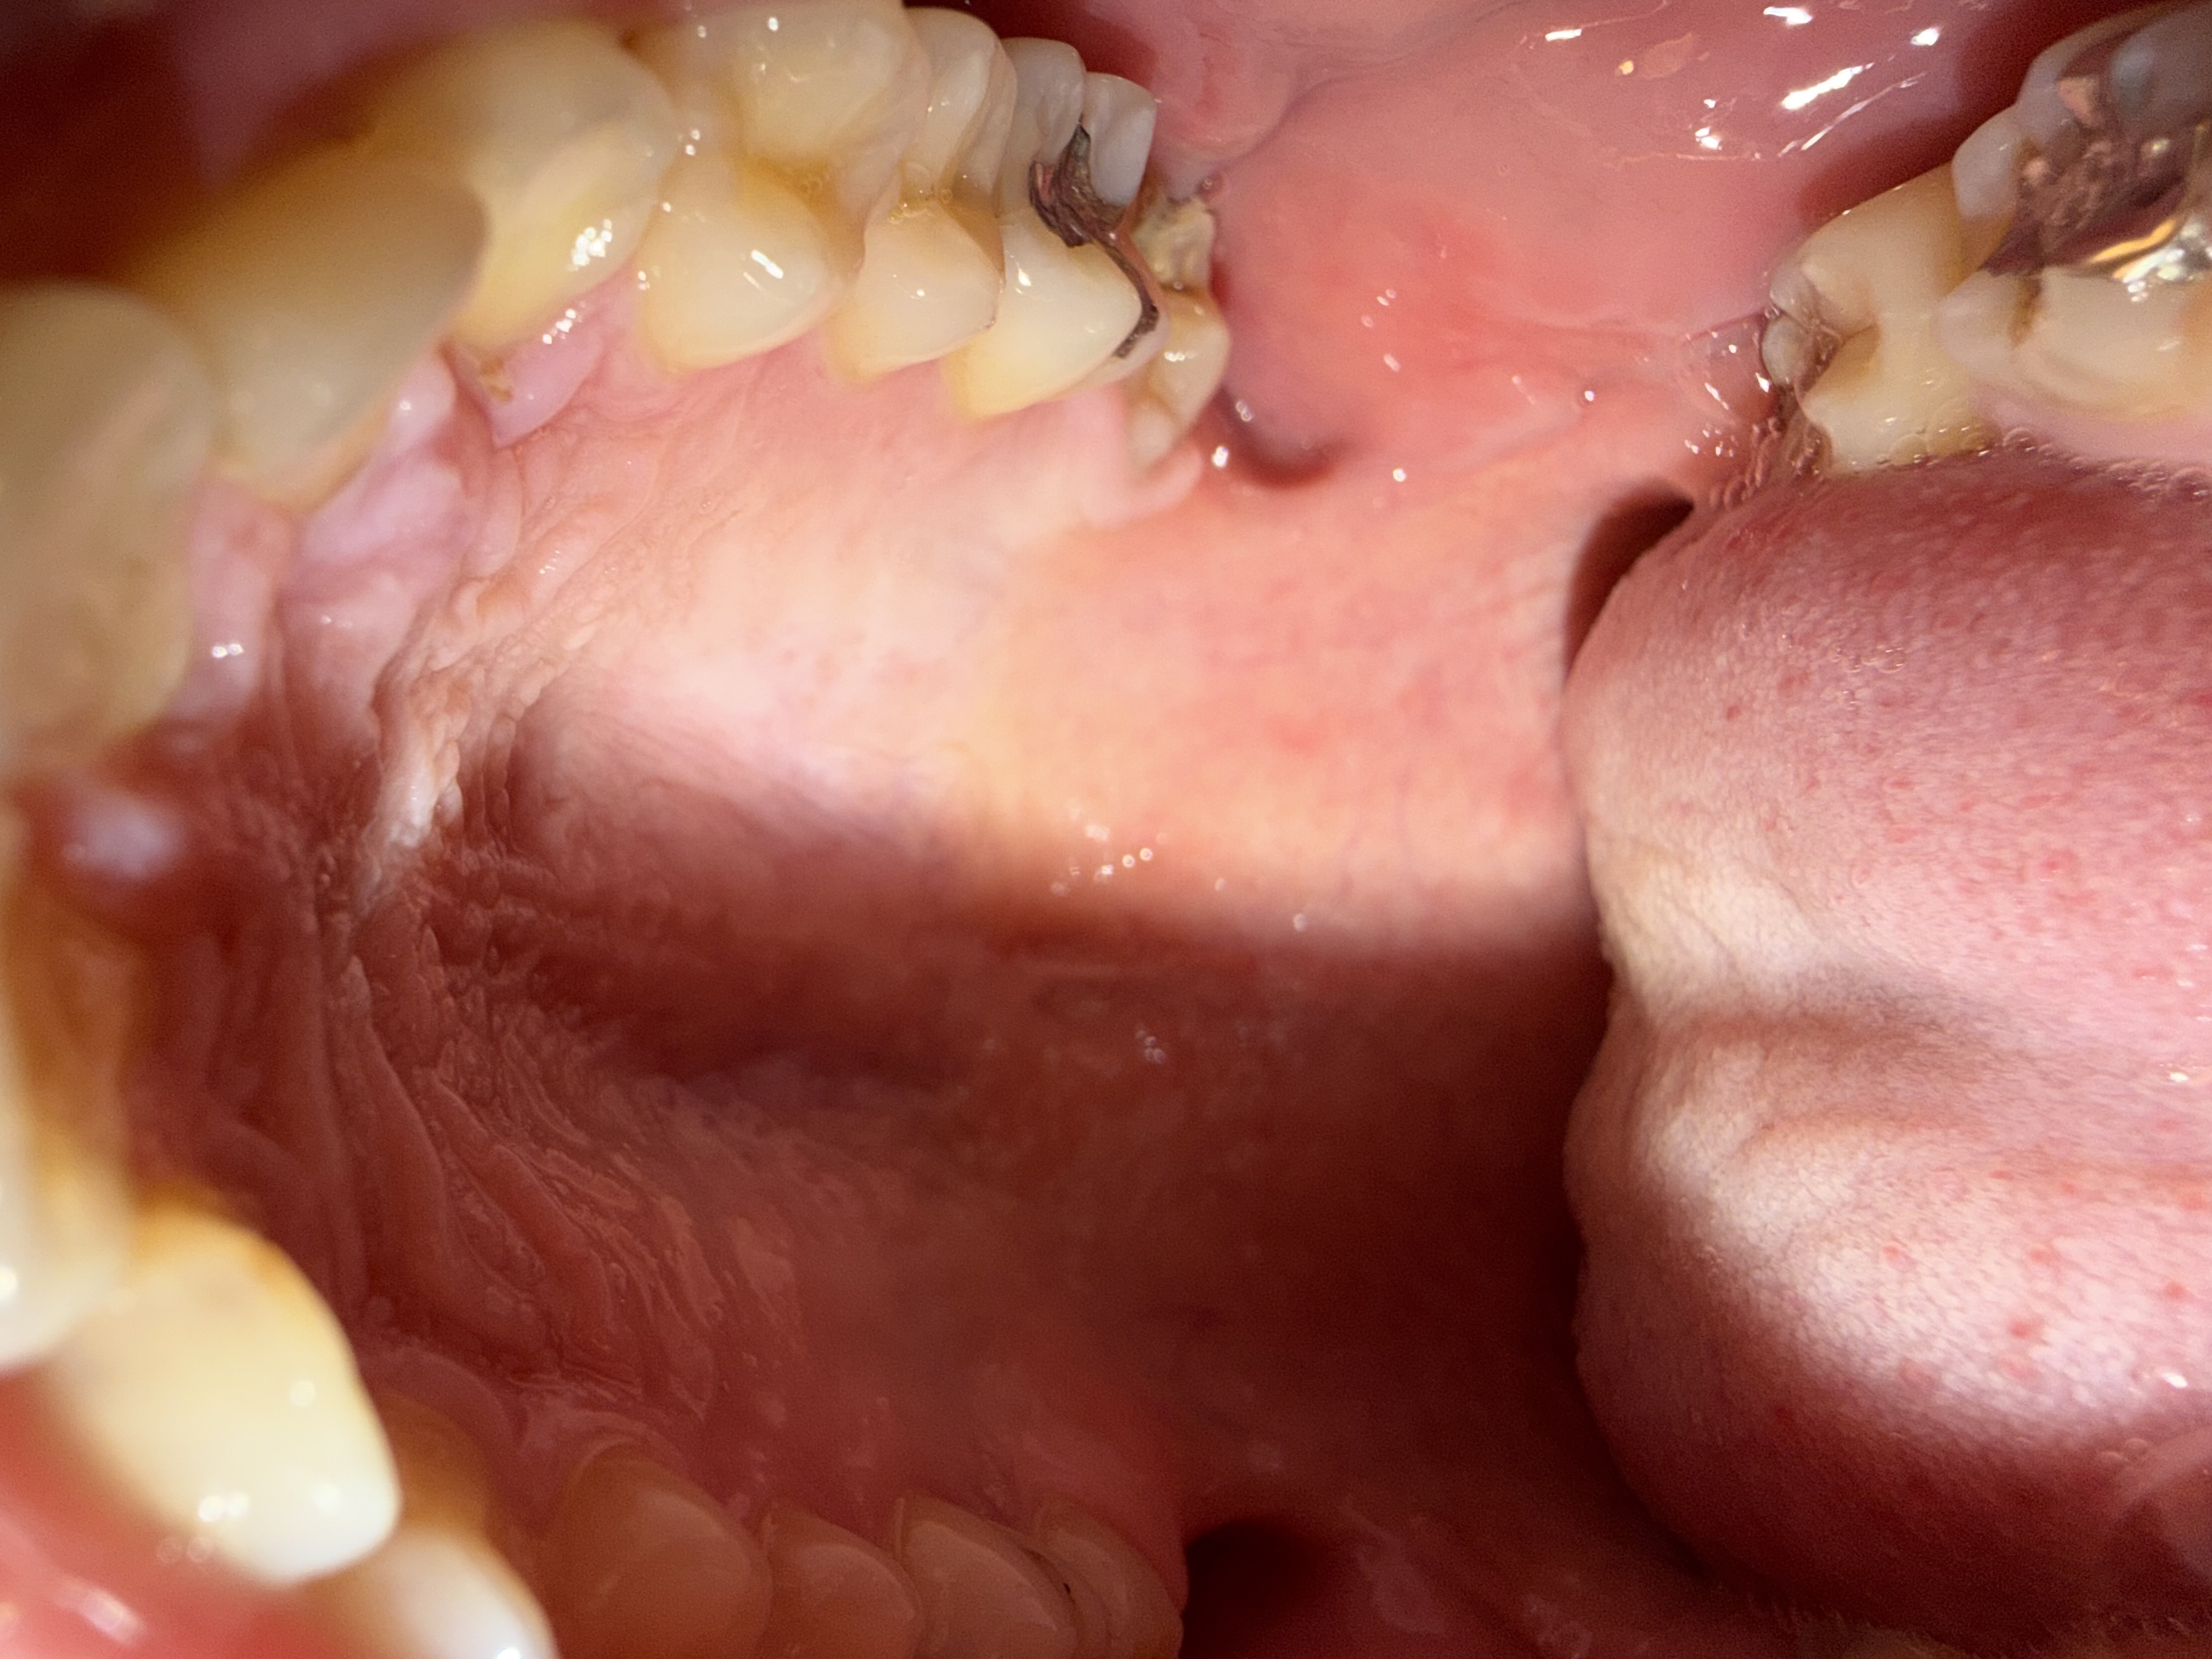

歯茎に白くて硬いしこりのようなものができました。